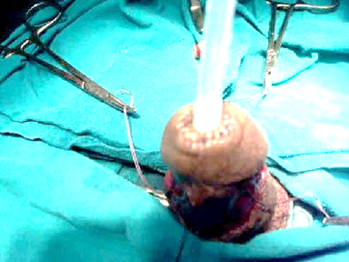

33 patients were managed by transverse penile island flap (with glans cap technique in 22 patients and split glanuloplasty among the other 11 patients), 4 patients were managed by Orandi repair, 3 patients had buccal mucosal graft, and the last 3 patients (LS) treated by 2 stages repair buccal graft.  All urethroplasties were performed by a single surgeon. In the first 22 patients, exposure was done through a short transverse incision on the ventrum of the penis 0.5cm proximal to the coronal sulcus. The glans was dissected in the plane between the glans and corpus spongiosum to the site of the meatus as in supplementary Figure S1A. The incision was created ventrally and lateral around the urethral meatus down to the sub-urethral plane to connect with the proximal plane of dissection over the corpus spongiosum, so easy to access all the strictured fossa navicularis without disturbance of the glanular shape. A tunnel was created between the glans and the urethra and ventral stricturotomy along the strictured fossa navicularis till the healthy penile urethra as in Figure S1B. A ventral transverse penile island skin flap was outlined with a dimension according to the urethral caliber and length needed in Figure S2. Elevation of the ventral aspect of the glans with stay suture so all the strictured fossa navicularis could be exposed. The transverse penile island flap was rotated 90 to be vertically oriented over the strictured segment. The flap was sutured to the urethral edges starting proximally to distally till the meatus with interrupted 6-0 Vicryl sutures as in Figure S3A-S3B. Dartous layer was sutured over the anastomotic line. The elevated glans was fixed to the underneath tissues in its place so that its configuration was not disturbed. The subcoronal incision was approximated with 6-0 Vicryl. A suitable silicone urethral catheter was inserted for 3 weeks.

Figure S1A Plane of dissection created between the glans and the corpus spongiosum.

Figure S1B Ventral stricturotomy of the fossa navicularis and meatus.

Figure S1 Plane of dissection and ventral stricturotomy.